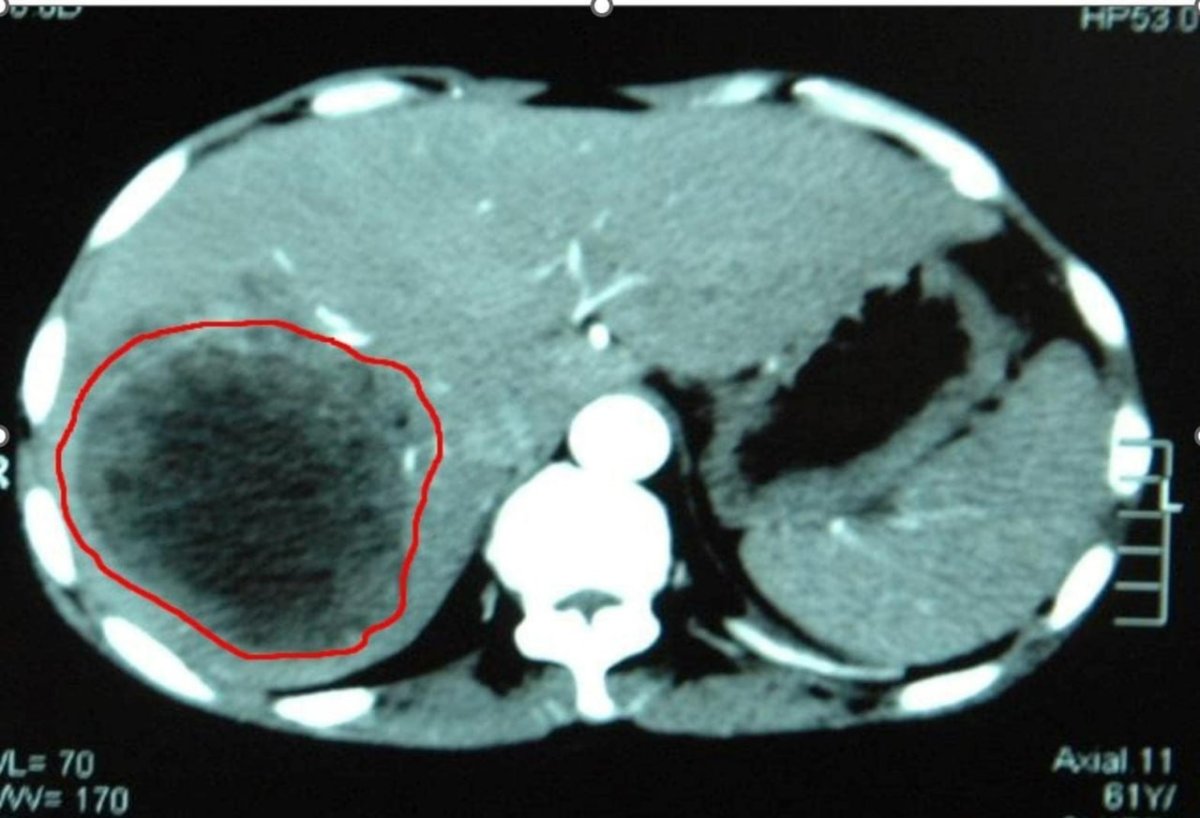

Новообразование занимало 70% всей печени, тесно связываясь с желчным пузырем и общей печеночной артерией, а вес гигантской опухоли составлял 6 кг. Она сдавила полую вену, желчный пузырь с протоками и крупные сосуды печени, полностью поглотив ее правую долю.

Как отмечает специалист, удалять такую гигантскую опухоль нужно полностью, постаравшись не нарушить ее целостность, в противном случае риск рецидива крайне высок. Сделать это непросто именно из-за больших размеров образования, отсутствия рабочего пространства в брюшной полости, тесного прилегания к крупным сосудам и значительно нарушенной анатомии. Любое неосторожное движение может привести к массивному кровотечению и нештатной ситуации.